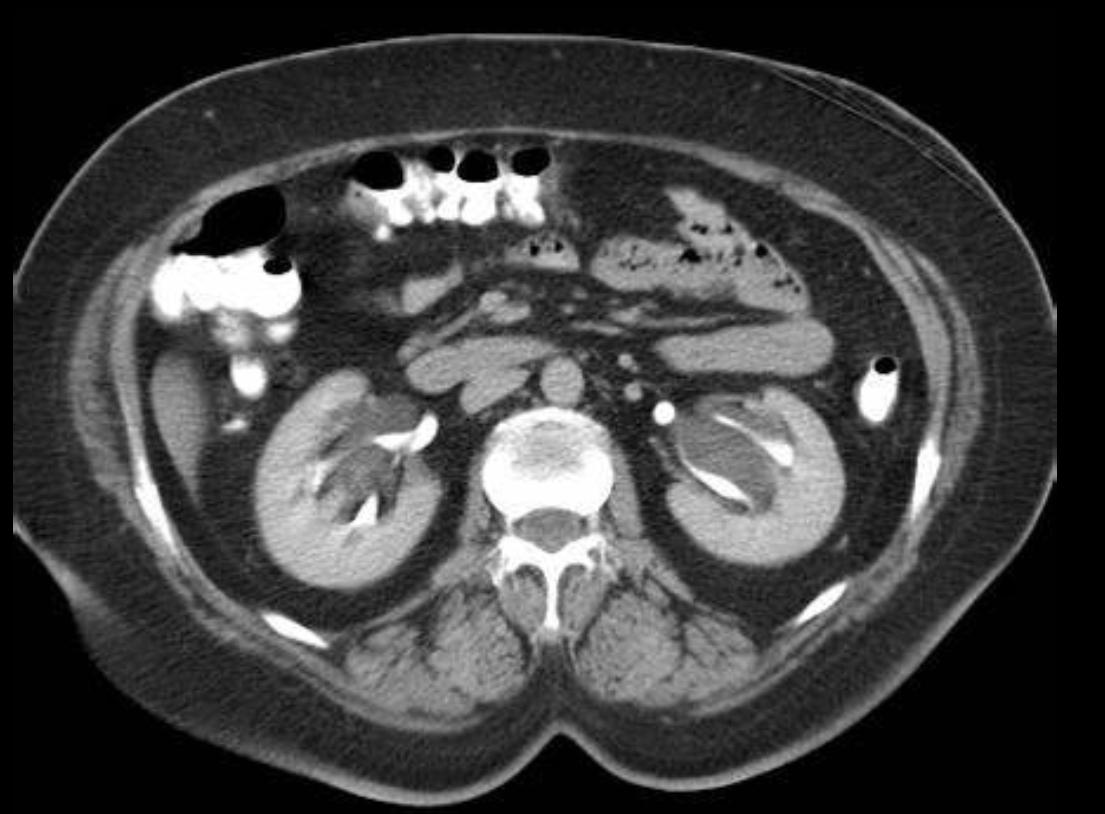

有的时候超声发现集合系统分离,可能不能分辨肾积水或肾孟旁囊肿,增强CTU明确诊断后,可能没有肾积水。增强CTU能够更加准确区分肾孟旁囊肿和肾积水 (以CT为准)。

(A)左肾矢状面和(B)横断面显示肾孟区域低回声(白头)提示肾积水。横断面上,这些区域并不相连(黄色双头箭头);增强CTU (C 和 D) 显示肾孟旁肿 (白头) 与造影剂填充的集合系统 (黄色头)